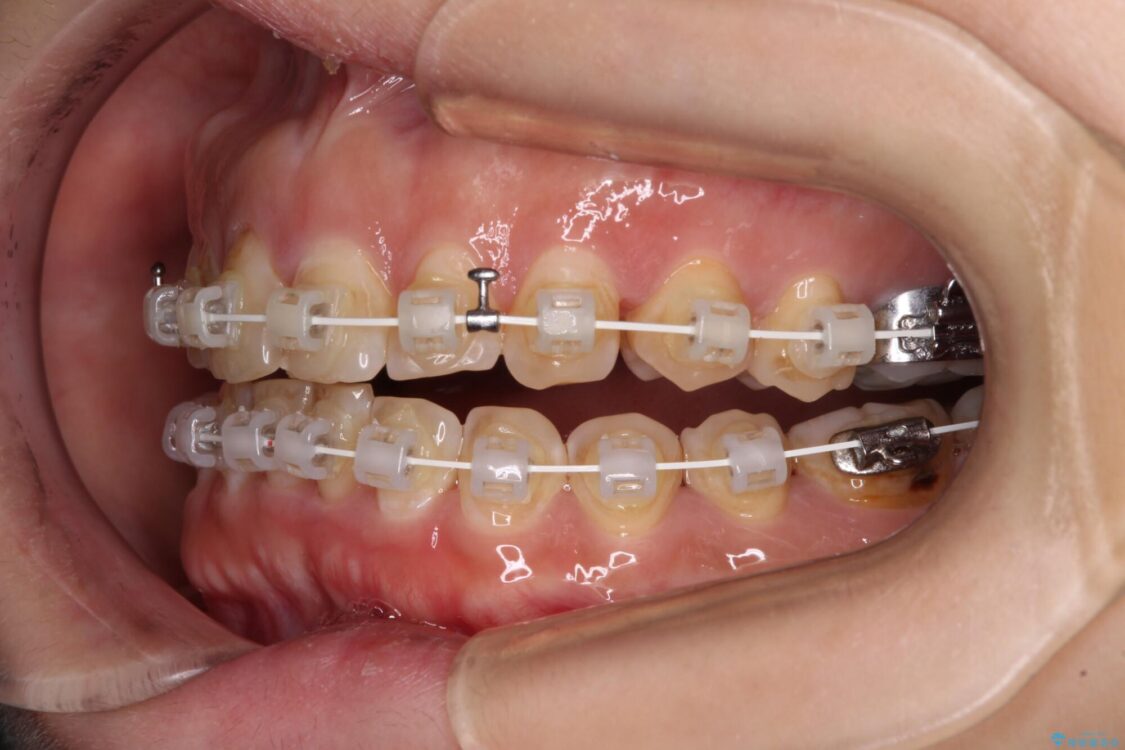

なるべく早めに治療を終えたいとのことで、補助装置を用いて上顎臼歯を後方に移動させ、同時にワイヤー装置にて整えることとしました。

治療途中

• 【モニター】飛び出た前歯を整えたい ワイヤー矯正治療 治療途中画像